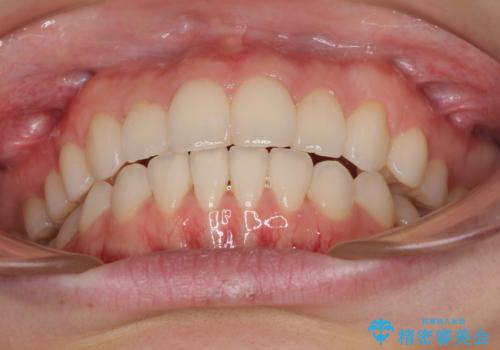

毎日しっかりと装着してくださったので、概ねシミュレーション通りに歯を移動させることができました。

治療前には接触することのなかった上下の前歯が接触するようになり、食事の際前歯でものをかみ切れるようになりました。

気にしていた口元の印象が改善され、患者様には大変満足していただきました。